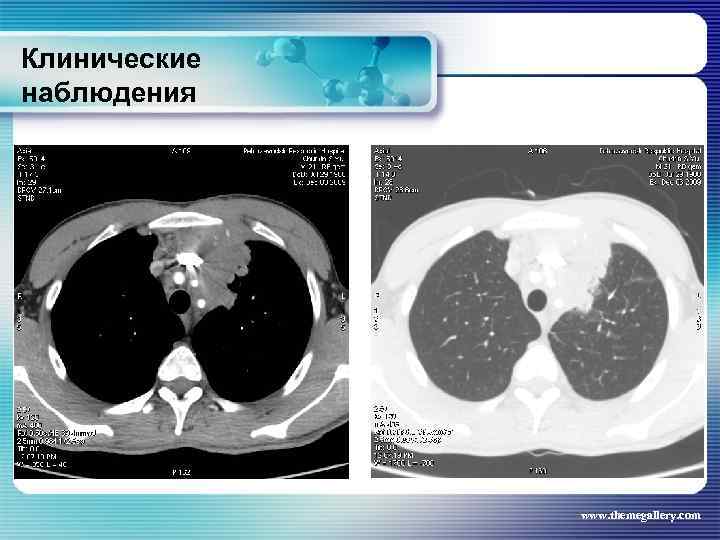

Клинические наблюдения Больной Ч. , 1988 г. р. Заболел 2 года назад, когда, после перенесенного ОРВИ, заметил увеличение шейных лимфатических узлов. К врачу не обращался. Спустя 3 месяца на медицинской комиссии обращено внимание на шейную лимфоаденопатию, направлен на рентгенографию органов грудной полости, выявлены изменения в средостении. Госпитализирован для обследования в гематологическое отделение, где была выполнена биопсия шейных лимфатических узлов и диагностирована лимфома Ходжкина. Вариант нодулярного склероза Gradе II. При лабораторном обследовании умеренно выраженные показатели активности процесса. При лучевом обследовании (рентгенограммы, УЗИ, КТ) выявлены следующие изменения: www. themegallery. com

Клинические наблюдения Больной Ч. , 1988 г. р. Заболел 2 года назад, когда, после перенесенного ОРВИ, заметил увеличение шейных лимфатических узлов. К врачу не обращался. Спустя 3 месяца на медицинской комиссии обращено внимание на шейную лимфоаденопатию, направлен на рентгенографию органов грудной полости, выявлены изменения в средостении. Госпитализирован для обследования в гематологическое отделение, где была выполнена биопсия шейных лимфатических узлов и диагностирована лимфома Ходжкина. Вариант нодулярного склероза Gradе II. При лабораторном обследовании умеренно выраженные показатели активности процесса. При лучевом обследовании (рентгенограммы, УЗИ, КТ) выявлены следующие изменения: www. themegallery. com

Клинические наблюдения www. themegallery. com

Клинические наблюдения www. themegallery. com

Клинические наблюдения www. themegallery. com

Клинические наблюдения www. themegallery. com

Клинические наблюдения www. themegallery. com

Клинические наблюдения www. themegallery. com

Клинические наблюдения www. themegallery. com

Клинические наблюдения www. themegallery. com

Клинические наблюдения www. themegallery. com

Клинические наблюдения www. themegallery. com

Клинические наблюдения www. themegallery. com

Клинические наблюдения www. themegallery. com

Клинические наблюдения Тот же пациент На основании выполненных исследований сформулирован клинический диагноз: лимфома Ходжкина, нодулярный склероз Grade II, III A E S стадия с поражением шейных, заднешейных, надключичных лимфатических узлов, средостения с прорастанием в левое легкое и плевру слева, внутригрудных лимфатических узлов, абдоминальных лимфатических узлов, селезенки. За время наблюдения проведено 8 циклов BEACOPP. На этом фоне достигнута в марте 2010 года парциальная ремиссия. При лучевом обследовании выявлена положительная динамика изменений. www. themegallery. com

Клинические наблюдения Тот же пациент На основании выполненных исследований сформулирован клинический диагноз: лимфома Ходжкина, нодулярный склероз Grade II, III A E S стадия с поражением шейных, заднешейных, надключичных лимфатических узлов, средостения с прорастанием в левое легкое и плевру слева, внутригрудных лимфатических узлов, абдоминальных лимфатических узлов, селезенки. За время наблюдения проведено 8 циклов BEACOPP. На этом фоне достигнута в марте 2010 года парциальная ремиссия. При лучевом обследовании выявлена положительная динамика изменений. www. themegallery. com